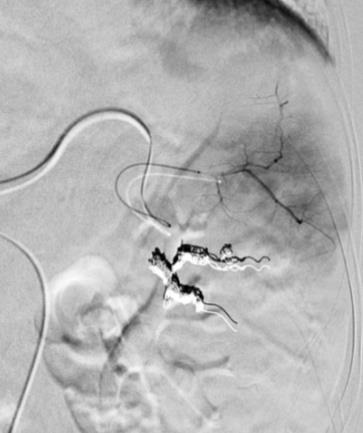

2. 段栓塞(弹簧栓子或微粒) 部分脾栓塞技术2:段栓塞

周围栓塞与段栓塞比较